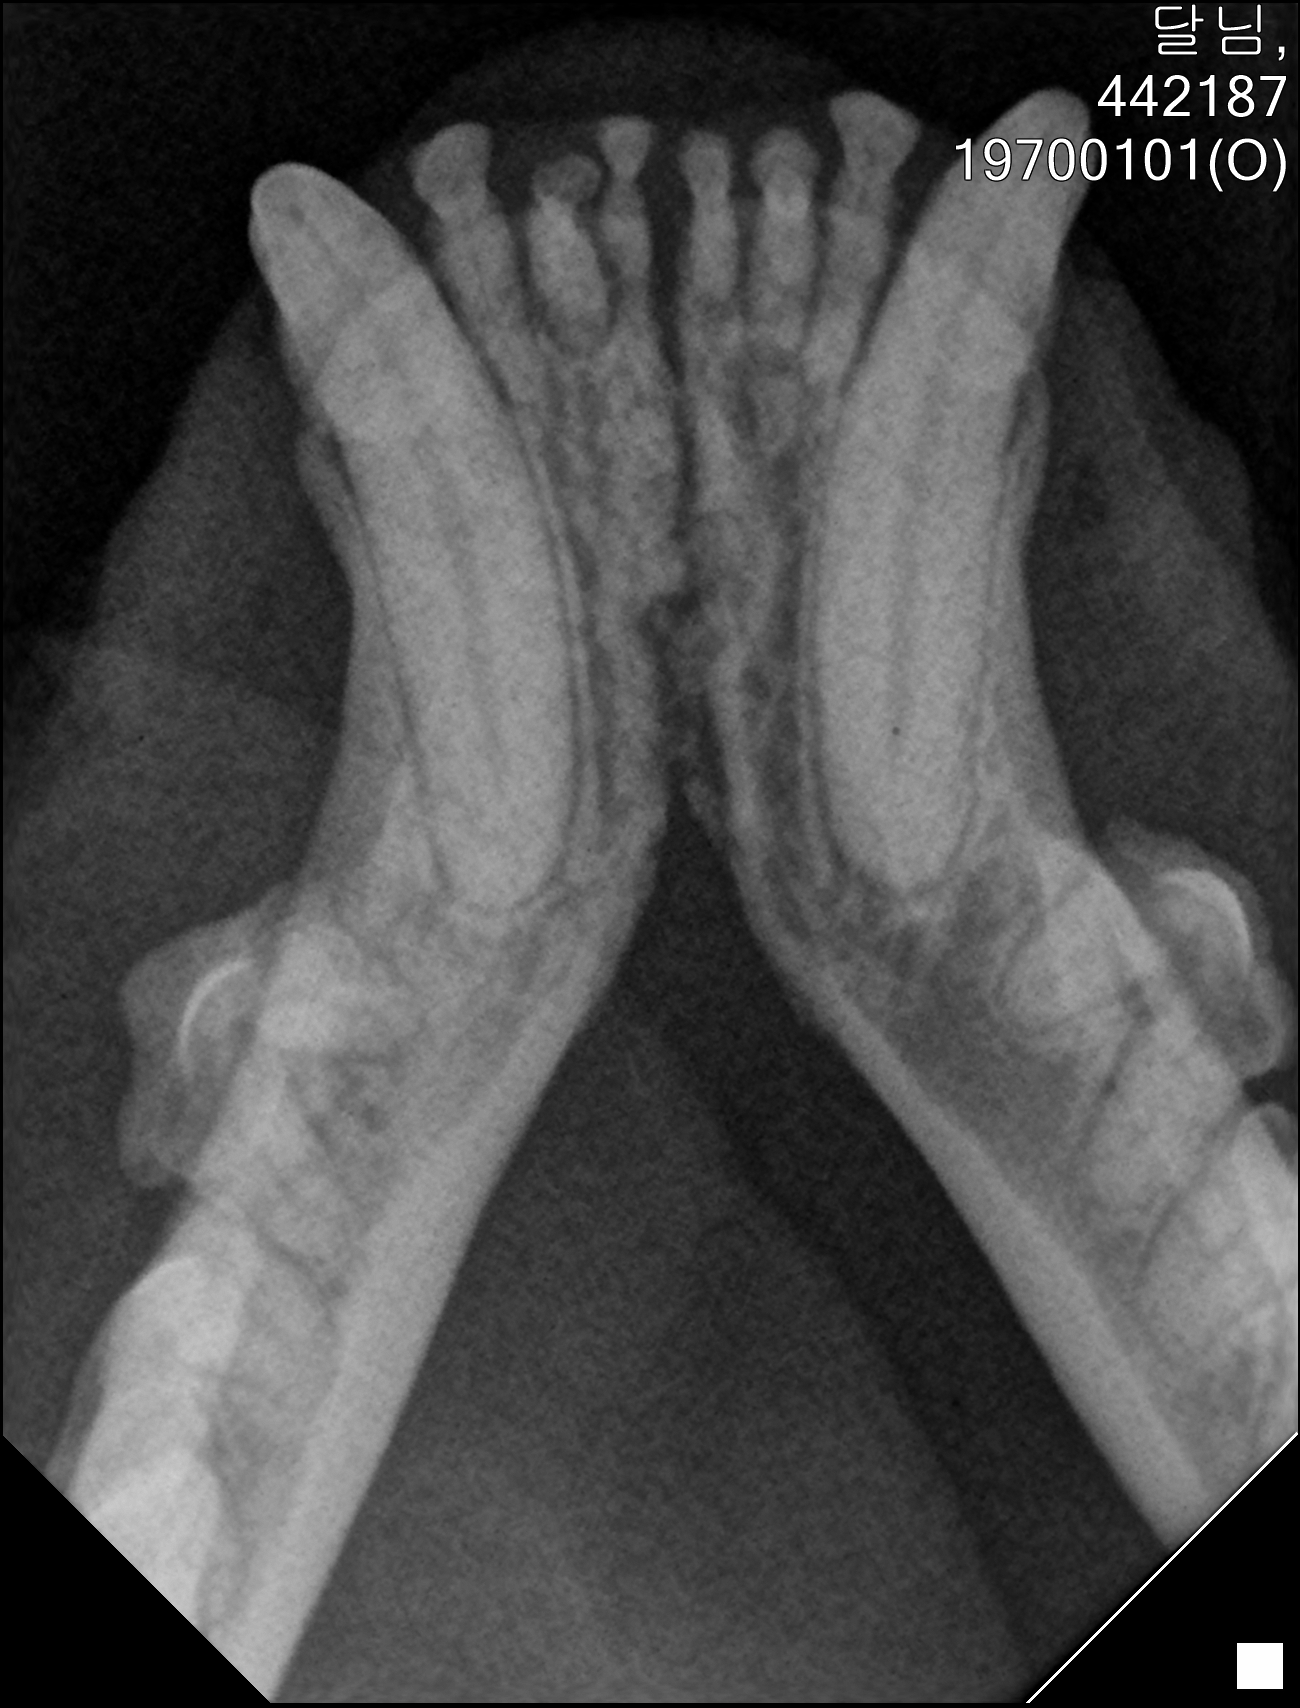

| 치료과정 | 달님이를 병원에 데려갔을때 거의 한달 가까이 먹질 못했기 때문에 몸무게는 2키로 초반대로 나갔고 마취하고 검사할수있는 상태가 아니였기 때문에 피검사를 통해서 간단히 검사후 입원하기 시작했습니다 탈수증세가 너무 심했고 수액을 맞으면서 자발식을 찾으려 했지만 달님이는 전혀 먹질 않았고 입원기간도 길어지게 되었습니다 그 와중에 청천벽력같은 소리를 듣게되었습니다 신장수치가 좋지않아 신부전이라는 결과였습니다 손도안타는 이아이를 제가 과연 케어할수있을까 너무 너무 걱정이였고 눈물이 앞을 가렸습니다 하지만 우선 체력을 회복한후 걱정은 나중에 하기로하고 달님이 치료에 집중하기 시작했습니다 병원에서도 선생님들이 달님이를 강제 급여도 해주고 수액도 계속 맞고 보니 꽉 막혀있던 코에서 콧물도 나고 소변도 보기 시작했습니다 그리고 다시 검사를 하고나니 다행히 신부전은 아니고 지방간이라고 하였습니다 아마도 오래전부터 먹는양이 줄어들었고 최근에 들어 아예 먹질못해서 간이 망가졌고 황달증세가 생겼다고합니다 어떤 이유에서인지모르겠지만 달님이는 원래 호흡기도 안좋았고 항상 콧물과 재채기를 달고산 아이라 호흡기도 안좋았고 이빨상태도 안좋아 밥을 못먹기 시작했던거같습니다 우선 체력회복이 중요하기때문에 집에서 케어한후 간 회복후 추후에 발치를 하기로 하였습니다 집에 온후 달님이는 바로 사료를 먹기시작했습니다 아마도 병원이 싫어서 밥을 안먹었던 모양입니다 매일 처방식과 약을 먹이면서 살을 찌우기 위해 이것저것 달님이가 좋아하는 캔과 츄르를 바치기 시작했고 다행히 달님이는 매일 맛있는 밥을 먹으며 살이 찌기시작했습니다 한달되는 날 발치와 검사를 위해 병원에 가서 검사를 하였는데 달님이는 3.86키로로 몸무게도 상당히 늘었으며 검사결과 모든 수치가 좋아졌습니다 그리고 마취후 이빨상태를 보니 치주염이 심각했고 이빨은 어금니부터 송곳니까지 다 내려앉은 상태였습니다 입안은 구내염이 시작되었고 원장님은 송곳니도 지금도 안좋지만 나중에 되면 더 아퍼질꺼라며 전발치를 해야한다 하였고 저는 달님이과 전발치를하고 길에서 잘 살수있을까 너무 걱정이였지만 나중에 아파서 또 구조후 마취하는것보다 낫다고 생각했고 밥자리도 잘 되어있어 전발치하고도 잘사는길냥이들 많다고 들어서 전발치를하게되었습니다 달님이는 수술을 잘 마쳤고 퇴원후 달님이는 집에서 10일정도는 약먹고 회복해야하기때문에 집에서 좀더 케어한후 방사할 예정입니다 |